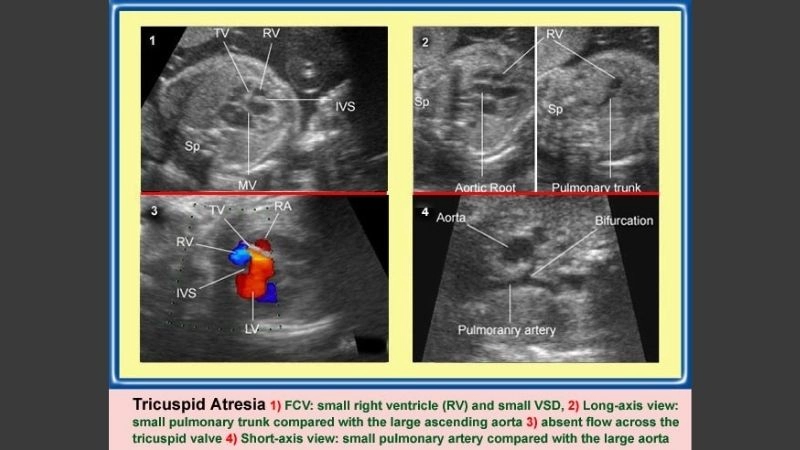

Images visual examples of hypoplastic right heart syndrome (HRHS)

Hypoplastic right heart syndrome (HRHS) is a rare congenital heart defect where the right side of the heart is underdeveloped, impairing blood flow to the lungs.